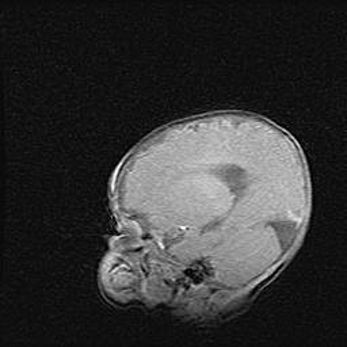

Неполная лизэнцефалия (пахигирия). Открытая гидроцефалия.

Возраст: 17 дней

Вес: 3110 г

Пол: мужской

Окружность головы: 33,5 см

Срок гестации: 35-36 недель

Лизэнцефалия—недоразвитие корковой пластинки и мозговых извилин в результате нарушения миграции нейронов коры. Поверхность мозговых полушарий гладкая. Микроскопически выявляется отсутствие нормальных слоев коры и скопление групп нейронов в подкорковом белом веществе.

Пахигирия—уменьшение числа вторичных извилин. В пораженном полушарии нервные клетки образуют толстый недифференцированный слой с неправильно расположенными нервными волокнами и группами гетеротопных клеток. Нервные клетки незрелые. Белое вещество истончено. При этом нередко аномально развит корково-спинномозговой путь.